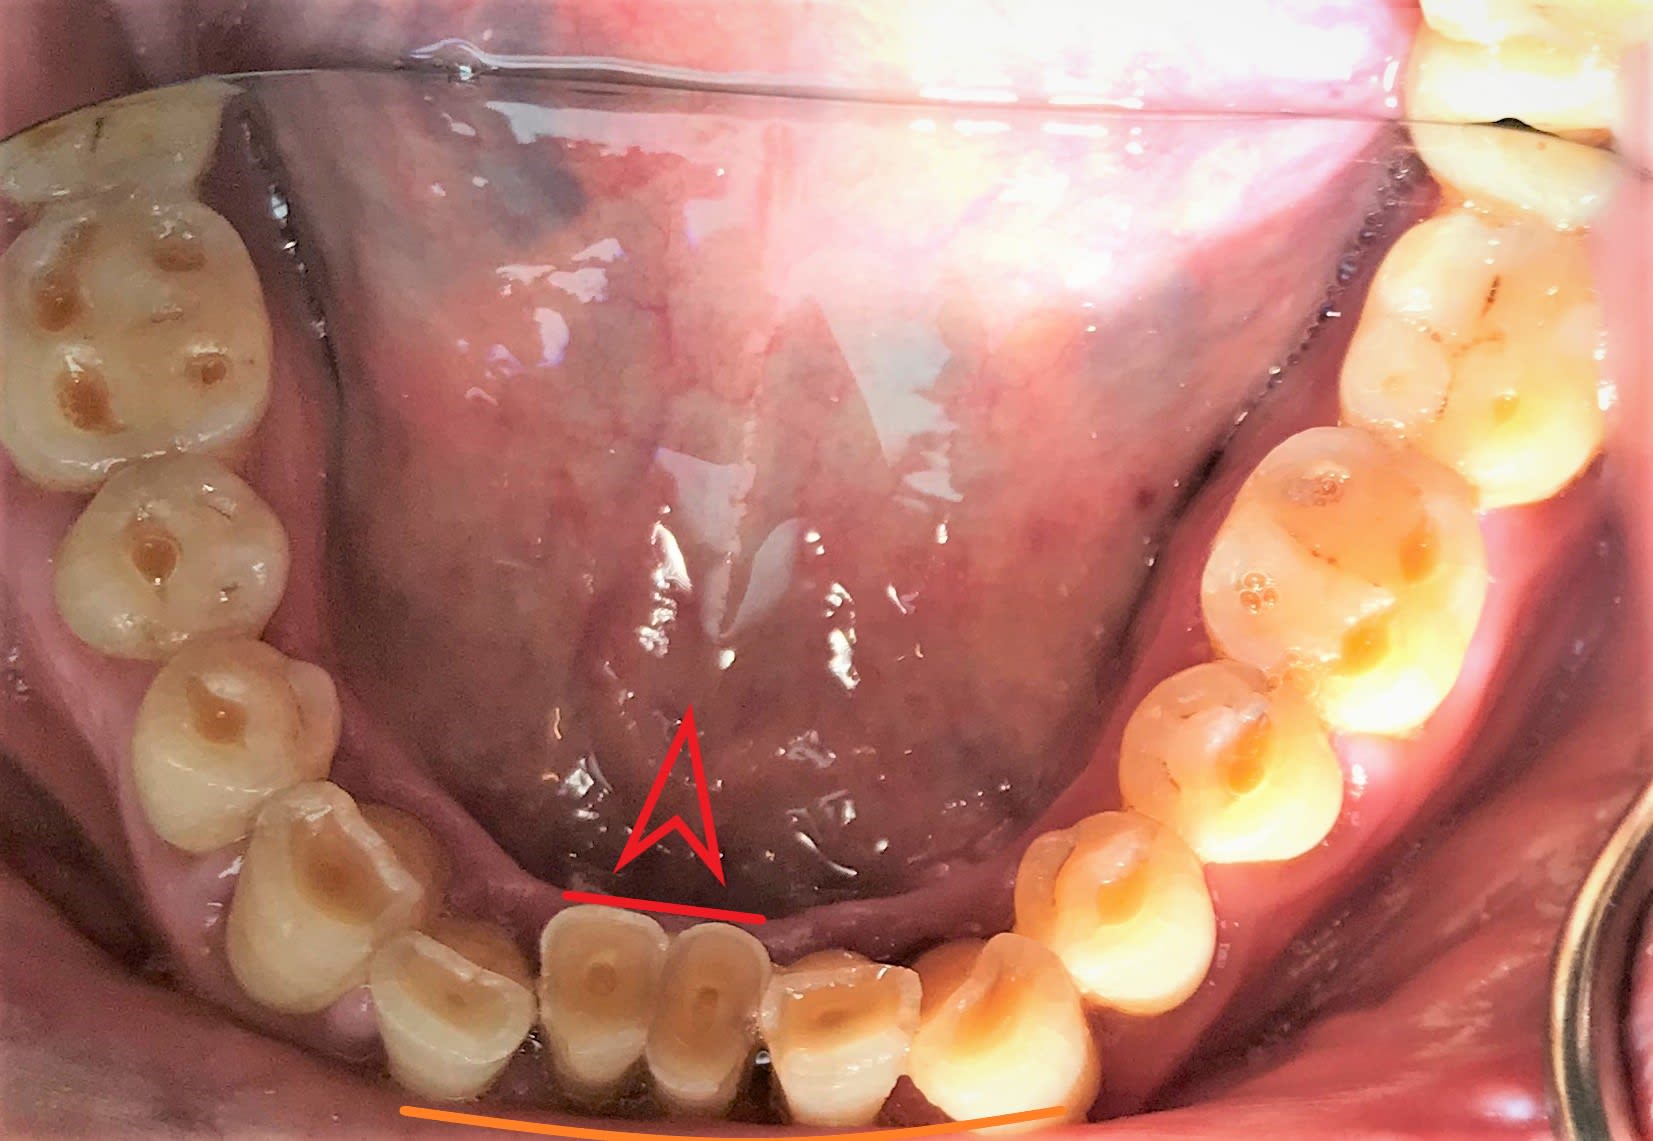

Non je trouvais que c’ était intéressant de montrer des usures de dents chez une personne qui a conservé quasi toutes ses dents au bout de 80 ans. C’est assez rare de voir des personnes âgées de 80 balais avec toutes leurs dents

Oui mais bon est-ce qu’il va aller jusqu’à 100 ans ? :))) Dans l’idéal il faudrait lui refaire une belle anatomie dentaire. Franchement je me sentirais comme un voleur si je m’amusais à lui faire tout ça surtout qu’il vient juste pour un contrôle sans aucune plainte . il prend des anticoagulants, du coup je lui ai limé les bords tranchants des dents pour qu’il ne se coupe pas. Il n’a même pas de sensibilité en plus.

Oui alors là pour le coup je ne suis pas d’accord. Elles sont plates parce qu’elles sont usées. Ça n’est pas pour une «  bonne raison ».

Quand l’articulation de la hanche est trop usée. Qu’est ce qu’on fait ? On la change par exemple. Quand tu uses tes pneus de voiture... tu laisses tes pneus usés ou bien tu les change ? Avec des pneus usés tu manies plus facilement ta voiture dans l’espace ou bien au contraire tu guides et tu arrêtes ta voiture plus aisément avec des nouveaux pneus? Et ben pour les dents c’est pareil . Quand le bruxo vous a usé les dents, on couronne. Et ben là dans l’absolu c’est pareil, normalement je devrais reconstituer l’anatomie des dents qui permettrait de reconstituer un guidage et envelopper les mouvements dans l’espace. Là je ne le fais pas juste parce qu’il a 80 balais , qu’il n’a pas de plaintes, qu’il est en fin de vie et que je n’ai pas envie de l’entuber.

Ouai enfin je me dis pas forcément. C’est une usure naturelle au bout de 80 ans . Je ne suis pas sûr qu’il faille chercher d’autres raisons

La limite entre l'usure normale et la pathologie est ici ténue. Cette usure, chez un mec de 40, c'est la cata. A 80 ans, tant que l'espérance de vie n'augmente pas drastiquement, c'est un bonheur.

Il semble assez normal pour une personne âgée d'avoir des pentes cuspidiennes à 0, non?